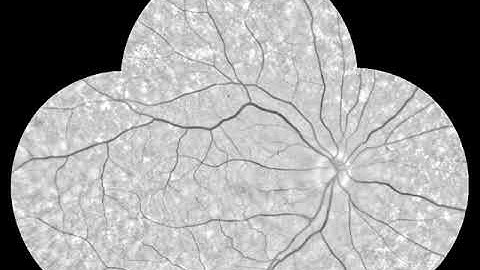

Image preprocessing demonstration